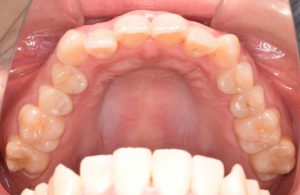

初診時(2022年12月)と装置撤去時(2025年9月)の写真です。

上あご

・上顎左右4抜歯

・上顎左右第一小臼歯抜歯

使用装置:上下顎マルチブラケット装置

アンカースクリュー